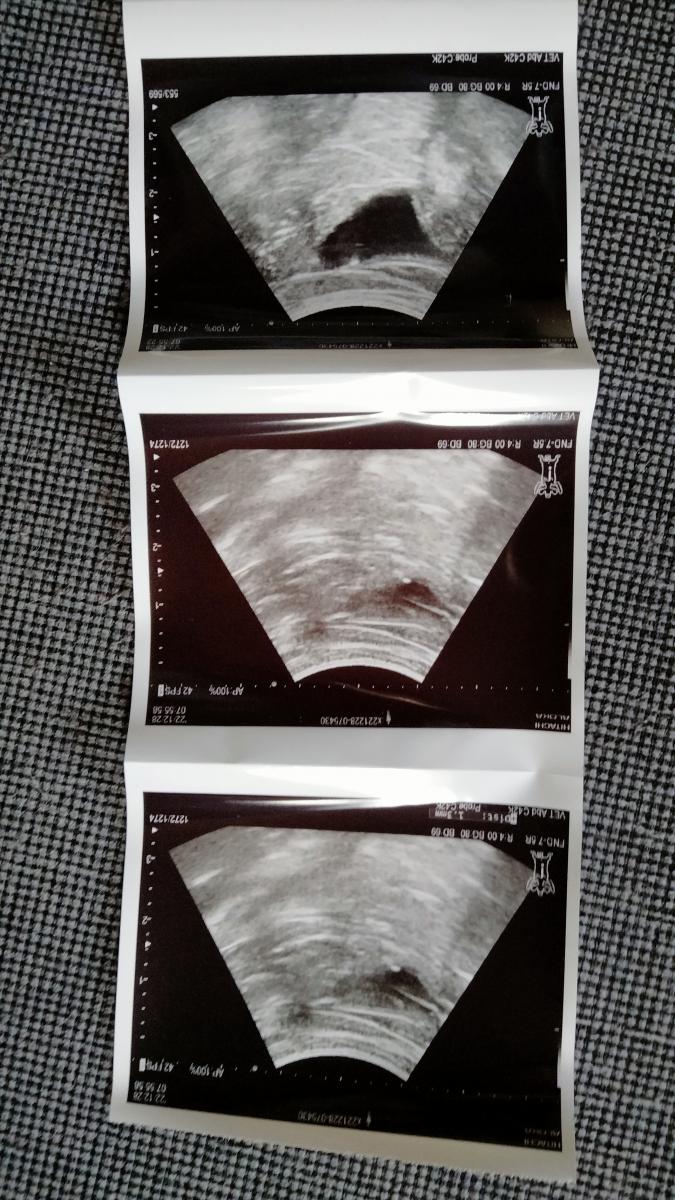

エコーにも 写っている

1.3ミリの膀胱の石を

下の写真が今日のうめ子の

尿検査結果と膀胱のエコーです

1.3ミリの膀胱の石が

悪さした時 血尿や頻尿になるそうです